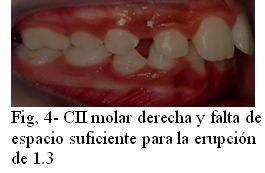

Se le realiza una completa historia clínica. Es una paciente sana desde el punto de vista general y regional, presentando alteraciones al examen clínico local. Se observa dentición mixta tardía, ausencia del órgano dentario permanente 4.2, persistencia del 8.3 y pérdida del equilibrio oclusal con desvío de línea media inferior a la derecha (Fig 2), por pérdida prematura del 8.2, contactando el 4.1 con el 8.3. No se observan ni se palpan alteraciones óseas en la zona. Presenta pequeños diastemas en el sector ánteroinferior que generan unos 3 mm de discrepancia dentaria positiva, insuficiente para ubicar el diente faltante (Fig. 3). La relación molar sagital es de clase II de Angle derecha e izquierda (Figs. 4 y 5), con falta de espacio suficiente para la erupción y correcta ubicación del 1.3 (Fig. 4).

Fig. 2 Línea media inferior desviada a la derecha y pérdida prematura del 8.2

Fig. 3 Pequeños diastemas, insuficientes para generar el espacio necesario para el 4.2